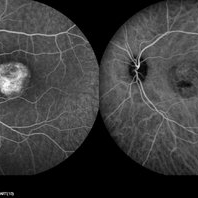

Best Disease Best DiseaseMar 9 2013 by Hamid Ahmadieh, MD FA and ICG Angiography of the left eye of a 49-year-old man with advanced Best disease. Photographer: Soodabeh Fooladin, Negah Eye Center, Tehran Imaging device: Heidelberg Spectralis Condition/keywords: Best disease, indocyanine green (ICG) angiography